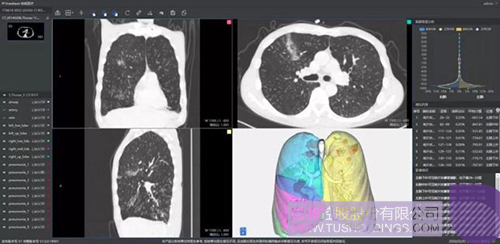

柏视医疗

640-3.jpeg

推出的新冠肺炎辅助筛查系统借助AI技术可行之有效地辅助大规模新冠肺炎病例的影像筛查工作。同时基于肺部结构快速智能分割,让医生对肺部病变情况一目了然。还可结合临床征象,自动生成符合最新型冠状病毒指南的结构化图文报告,辅助医生大幅提升诊断效率,同时提高诊断准确性。